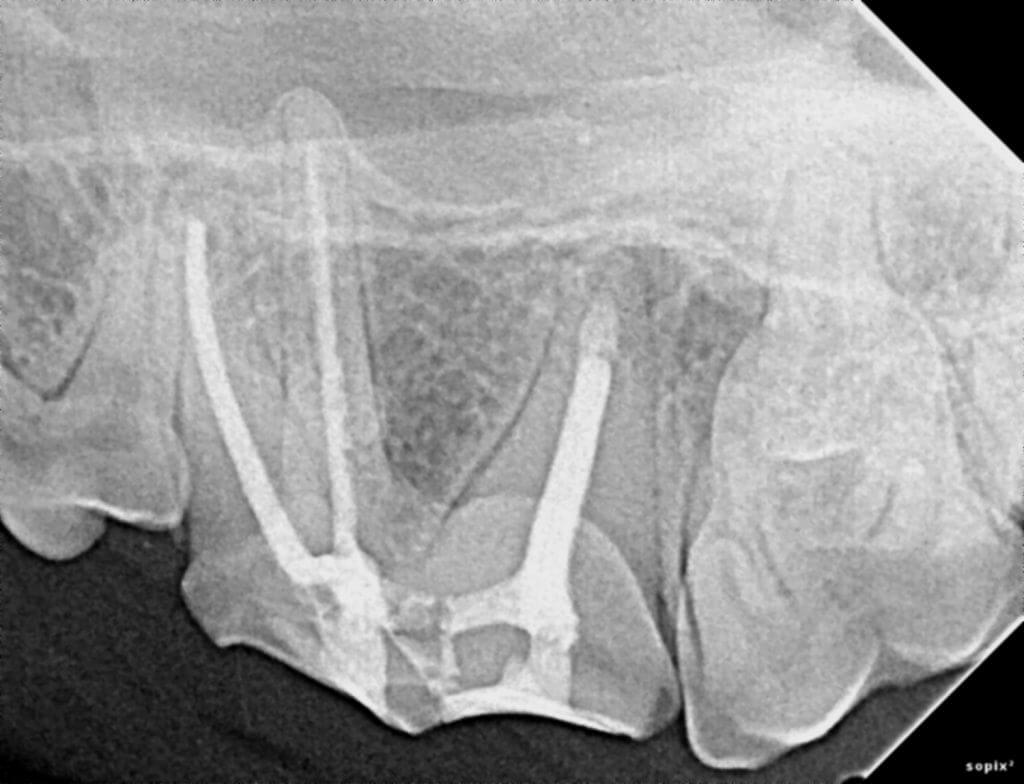

Dr. Hall begins with a thorough oral exam and dental radiographs to assess the tooth's condition. Our team uses digital X-rays and CBCT scans for detailed imaging, allowing us to identify hidden damage or infection beneath the surface.

If a root canal or pulp therapy is needed, our team removes diseased tissue from inside the tooth. The root canal is thoroughly cleaned, disinfected, and filled with a material that seals out bacteria. This technique lets your pet keep their natural tooth and resolve pain.

After the tooth is filled, we restore its function with a protective crown or composite restoration. The healing process is monitored through follow-up appointments, ensuring long-term results and excellent oral health for your pet.